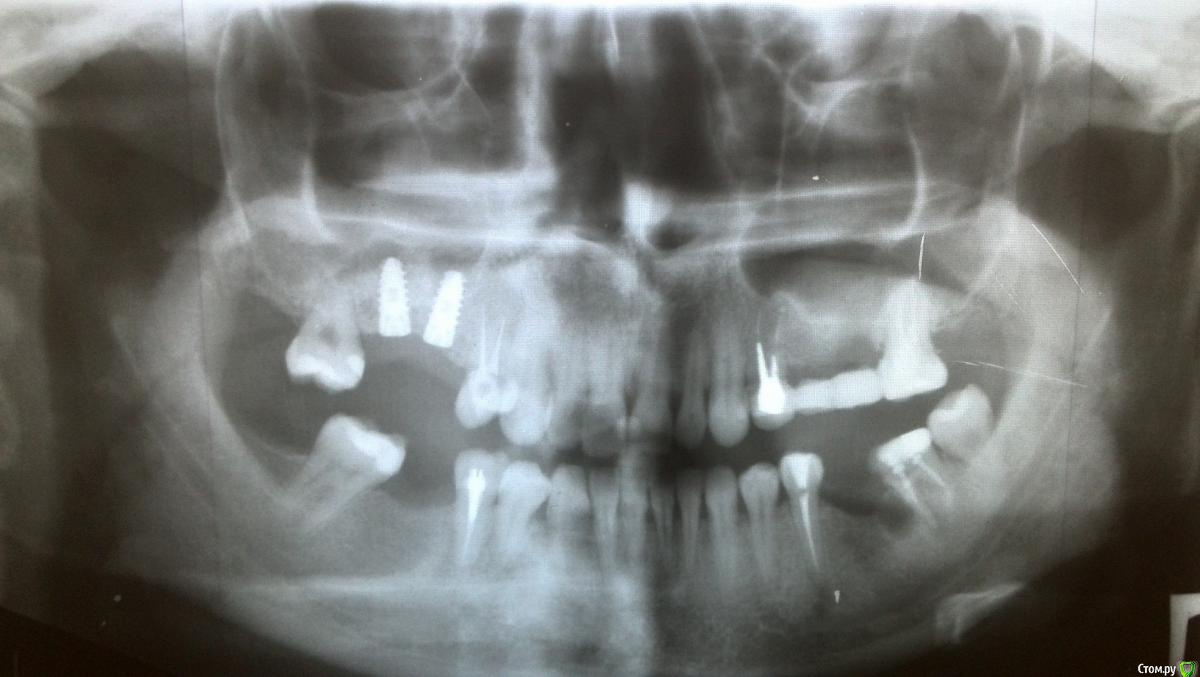

Анчетка Опубликовано 19 марта, 2015 Поделиться Опубликовано 19 марта, 2015 Здраствуйте, дайте пожалуйста консультацию1) 35 зуб необходимо перелечить ? плохо запломбирован канал, в снимках я не разбираюсь2) 37 понятно удалять- в хирургии задала вопрос, не ответил никто - через какое время туда можно поставить имлант? 3) на месте 36 нужно наращивать кость для имланта?4) 38 сегодня начал болеть при жевании -хотя не давно (месяц назад ) лечили кариес глубокий., почему может болеть?5) бело-желтый налет возле шва на десне после синуса -это в пределах нормы?И заранее ,Большое спасибо за уделенное время. p.s. неуверенна ,что нумерацию верно написала 1 Ссылка на комментарий

Scrabble Опубликовано 19 марта, 2015 Поделиться Опубликовано 19 марта, 2015 1)35-сделайте прицельный снимок, на этом ничего не видно 2)37-в зависимости от 36, там при удалении порезвились, нужна аугментация(хирурги поправят, если что) 3) см. 2 4) возможно обострение хронического пульпита или периодонтит-или иррадиация болей от 37 5) это фибрин. Всё норм. 1 Ссылка на комментарий

Гарриевич Опубликовано 20 марта, 2015 Поделиться Опубликовано 20 марта, 2015 1- по этому снимку точно не скажешь. Давно лечили зуб?2- это должен решать хирург, возможно сразу (КТ)3- скорее всего нужно, но есть вариант, что может и не потребуется (КТ)4- болит при жевании постоянно или в одной какой точке при определенном смыкании зубов? Ссылка на комментарий